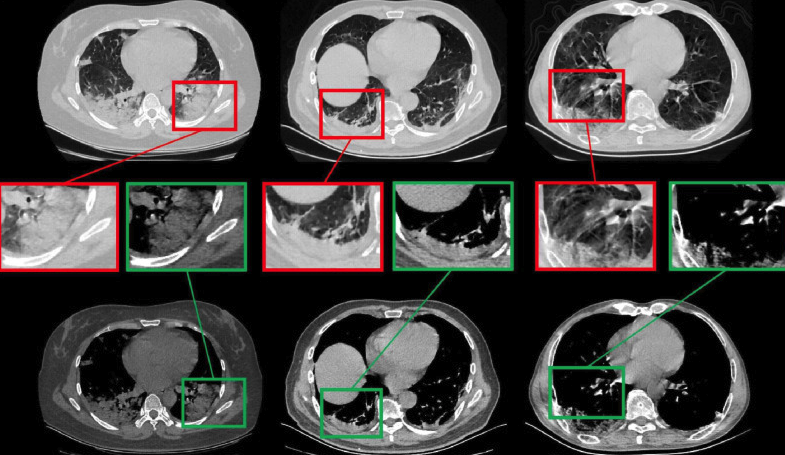

covid_image.png

COVID-19 Chest CT Image Segmentation Network by Multi-Scale Fusion and Enhancement Operations

Qingsen Yan, Bo Wang, Dong Gong, Chuan Luo, Wei Zhao, Jianhu Shen, Jingyang Ai, Qinfeng Shi, Yanning Zhang, Shuo Jin, Liang Zhang, and Zheng You

IEEE Transactions on Big Data, 2021